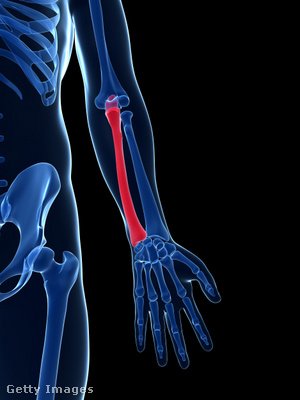

9. kérdés

Melyik csont látható kiemelve a képen?

singcsont

sípcsont

karcsont

A helyes válasz: singcsont